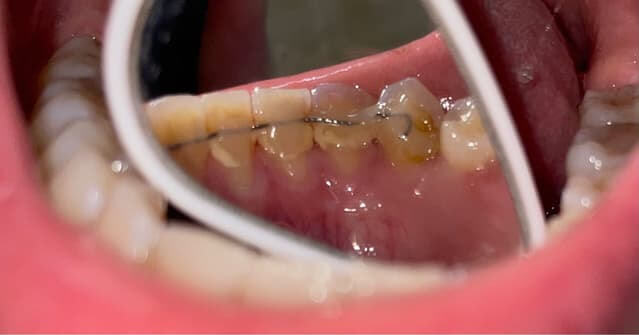

First, be clear on what “teeth cleaning” includes. In Hong Kong, most dentists provide a basic oral exam, ultrasonic scaling to remove tartar (calculus), and plaque removal. Depending on your condition, they may add polishing or air polishing, and sometimes recommend X‑rays (such as panoramic or bitewing films) to assess periodontal status and decay risk. In mainland China, some clinics market package deals, but what’s included varies. Larger regulated chains tend to be more standardized; others may separate and upsell items like air polishing, polishing, periodontal charting, or medicated irrigation. It can look “cheap” on the surface, but if your mouth needs additional procedures, your total cost, time, and effort can add up.

Next, consider hygiene and professionalism. Teeth cleaning involves ultrasonic scalers, hand instruments (curettes), saliva ejectors, and more. Sterilization and single-use disposables are critical. Wherever you go, do not be shy about checking: Is there a clear disinfection protocol? Are instrument pouches properly sealed and labeled? Are gloves and masks changed every time? Is the treatment room clean and orderly? Dental regulation and transparency in Hong Kong are relatively strong. In the mainland, there are also many qualified medical institutions, but you need to choose wisely: check licensing, reviews, dentist credentials, and whether the clinic openly publishes its infection control guidelines. Safety and professionalism should always come first.